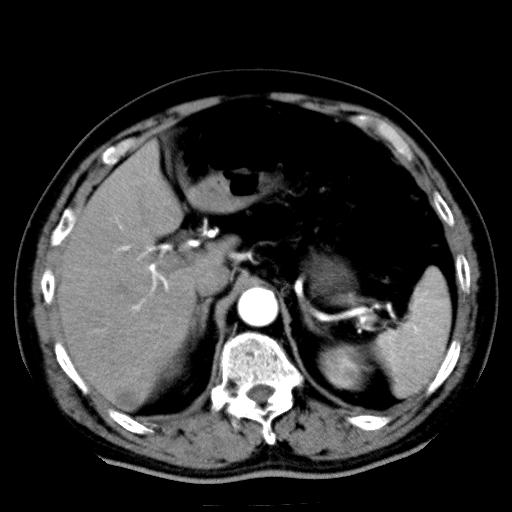

以下是引用zhctwbh在2008-8-23 14:20:00的发言:[br]囊肿合并出血

以下是引用zjb在2008-8-23 16:41:00的发言:[br]囊肿并出血可能性大。